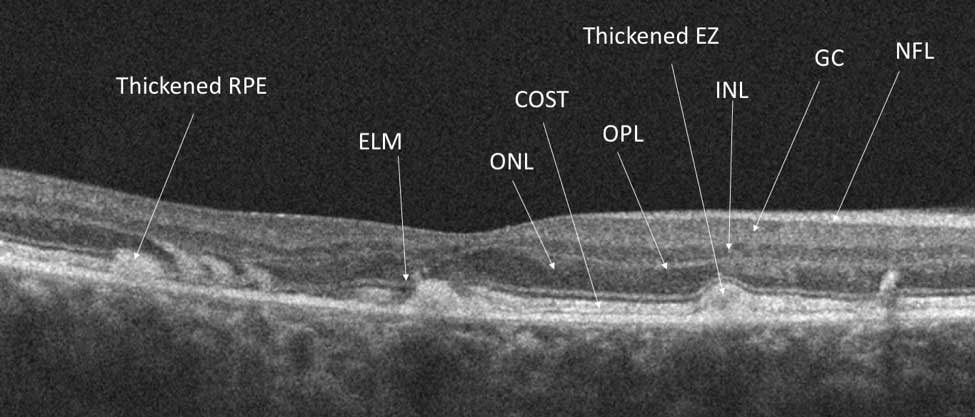

Here there is loss of the regular macular depression. There is a bright line present on the surface of the retina. In addition, there is separation of the retinal layers in the inner retina.

The patient was diagnosed with a schisis secondary to an epiretinal membrane. This complication is seen in over 50% of ERMs (video).

In any patient with intraretinal fluid consider the possibility of an epiretinal membrane causing a schisis.